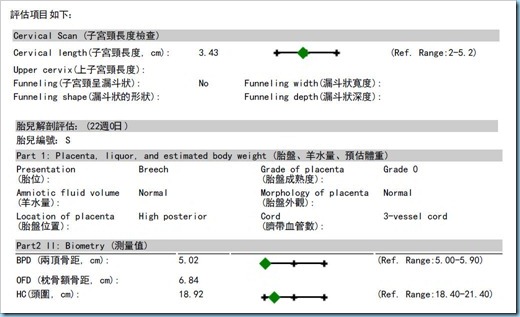

2013/03/01:產檢20W+4D..小朋友385g標準!!

右腎偏大~要追蹤~擔心!!!

Mama體重54.1Kg..小寶寶右腎0.83~左腎0.53cm~皆要追蹤!!!哎~~